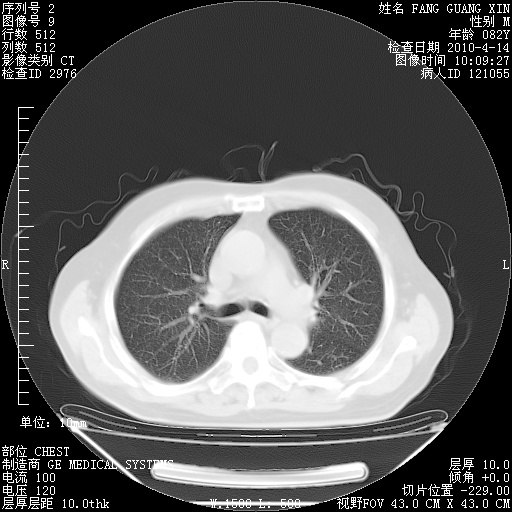

4月14日肺部CT

肺部CT平扫未见异常。